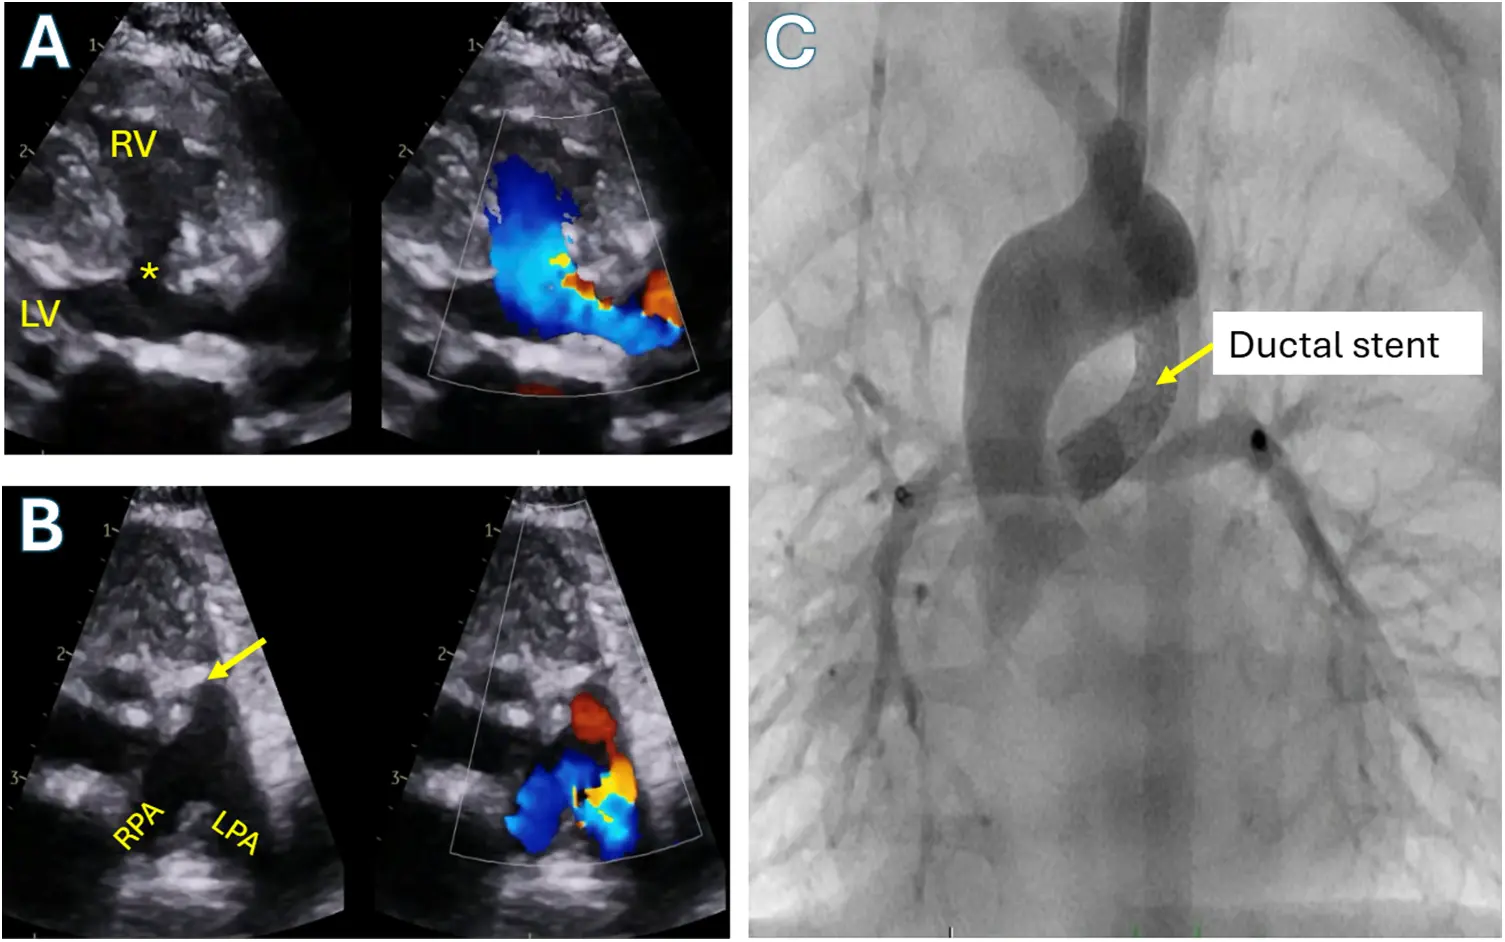

The medical management of unrepaired Tetralogy of Fallot is mostly limited to emergency situations. In the neonatal period, prostaglandin E1 infusion to reopen a closed ductus can be an important step in the resuscitation of a cyanotic, ductal dependent child. An example of an opened ductus can be seen in Fig. 5. Once past the neonatal stage with acceptable systemic saturations, most specialists recommend careful monitoring in the outpatient setting until the patient is ready for surgical repair. In the presence of a tet spell, the physiological underpinning of management is improving pulmonary blood flow. This is done by manipulating systemic and pulmonary resistance, increasing stroke volume, and decreasing the dynamic RVOT obstruction.

Figure 5: Tetralogy of Fallot with pulmonary atresia and confluent branch pulmonary arteries supplied by ductus arteriosus. A: Color compare transthoracic echocardiographic parasternal long axis view showing the large ventricular septal defect (asterisk) and overriding aorta. B: Color compare transthoracic echocardiographic parasternal short axis showing atretic pulmonary valve (arrow) with branch pulmonary arteries supplied by a ductus arteriosus (red flow). C: Anterior-posterior angiogram in the aorta demonstrating a stented patent ductus arteriosus supplying flow into the branch pulmonary arteries in the same patient. RV: Right ventricle; LV: Left ventricle; RPA: Right pulmonary artery; LPA: Left pulmonary artery